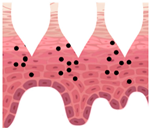

| Types of MNs | Solid MNs | Coated MNs | Dissolving MNs | Hollow MNs | Swellable MNs |

|---|---|---|---|---|---|

| Just before insertion |  |  |  |  |  |

| After application |  |  |  |  |  |

—MN loaded with active ingredients;

—MN loaded with active ingredients; —solid needle;

—solid needle; —dissolving/swellable needle;

—dissolving/swellable needle; —stratum corneum.

—stratum corneum.| Material | Characteristics | Cosmetic Benefits | 3D Printability |